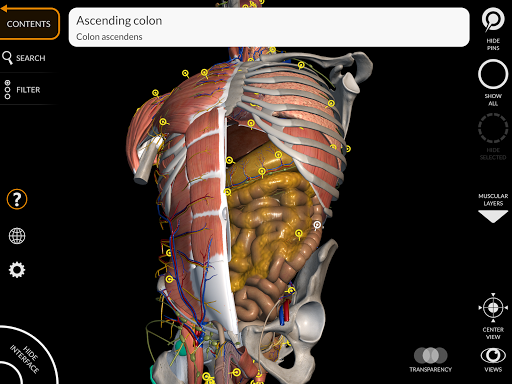

من خلال واجهة بسيطة وبديهية، من الممكن ملاحظة كل بنية تشريحية من أي زاوية.

تتميز النماذج التشريحية ثلاثية الأبعاد بتفاصيل خاصة ودقة تصل إلى 4K.

يسهل التقسيم حسب المناطق والمناظر المحددة مسبقًا مراقبة ودراسة الأجزاء الفردية أو مجموعات الأنظمة والعلاقات بين الأعضاء المختلفة.

• الجهاز الهضمي

• خيار إخفاء أو عزل نموذج واحد أو نماذج متعددة مختارة

• فلترة لإخفاء أو عرض كل نظام

• من خلال تحديد نموذج أو دبوس، يظهر المصطلح التشريحي ذي الصلة